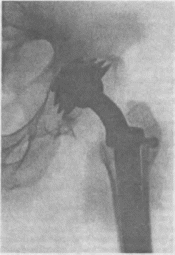

194.

Рентгенограмма

тазобедренного сустава после

эндопротезирования по Сивашу.